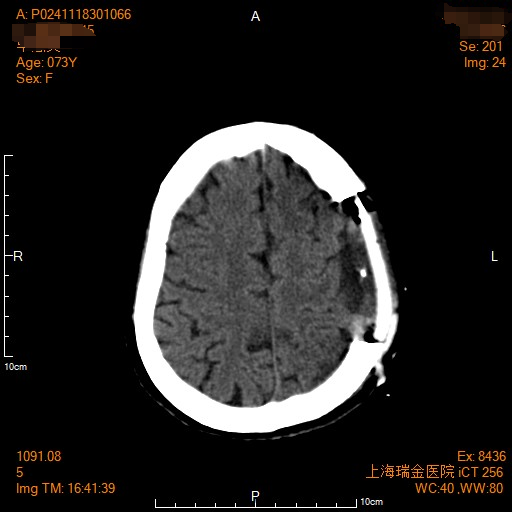

患者老年女性,于1988年察觉左顶皮下肿物,约2cm,否认头晕头痛、四肢麻木无力等不适,定期随访, 1997年因肿物进行性增大(约6cm),考虑脑膜瘤伴骨质破坏可能,行左顶头皮下肿物切除术,病理不详。术后未常规随访。202311患者自觉头胀,左顶可扪及皮下肿物(约2cm),202405患者出现左手掌麻木,20241021完善【头颅MR】示左侧额顶部头皮下肿块(55*32*41mm)伴相应颅骨骨质破坏,脑膜瘤不除外;右侧颞叶深部、颞极及左侧幕下散在异常强化灶,脑膜瘤?转移瘤?双侧基底节区、侧脑室旁及额顶叶多发 腔隙灶、腔梗灶,脑白质变性,老年性脑改变;副鼻窦炎症。现患者为进一步就诊,门诊收治入院。术前影像学资料如下:

术后安返病房,CT提示无殊,术后2日予以出院。